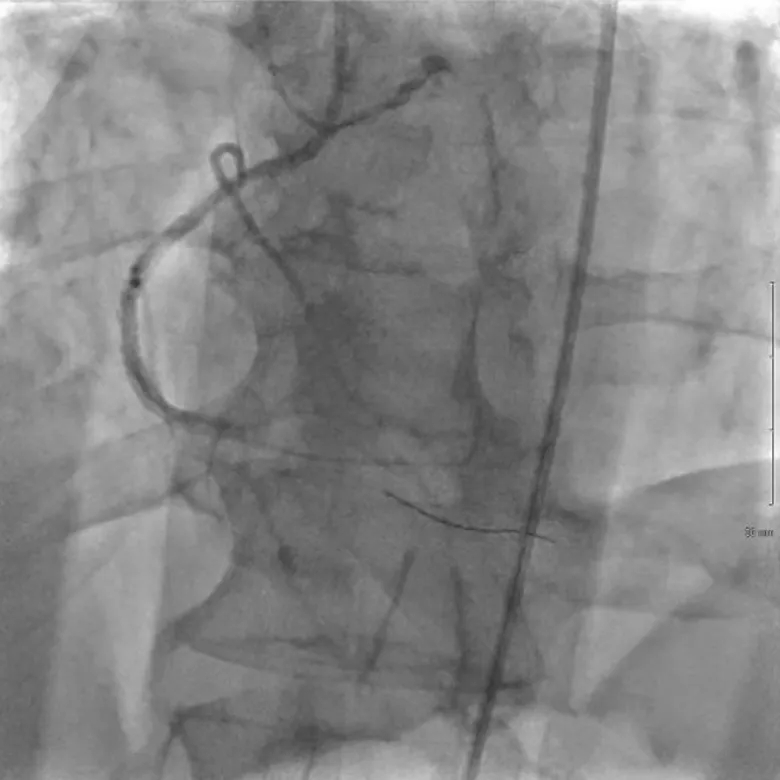

➤ 使用1.4mm导管以60-mJ/mm2能量密度,60 Hz频率进行ELCA。进行了6次激光治疗,期间使用标签外的造影剂,以最大限度地提高光力学性能,增强消融效果(图2)。

图2